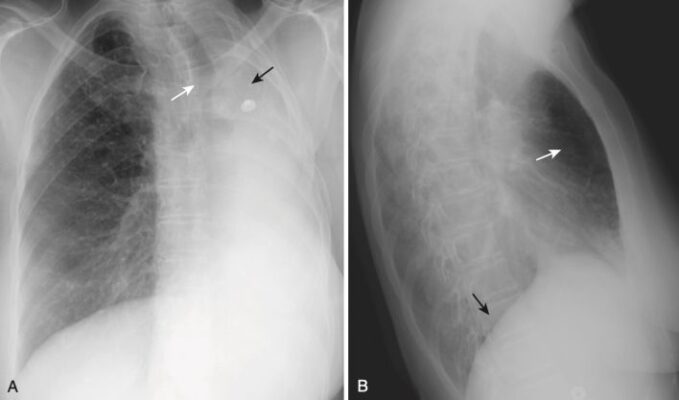

Xẹp phổi thùy trên bên phải (xem Hình 2)

- Trên phim X quang thẳng:

- Có sự dịch chuyển lên trên của rãnh liên thùy bé.

- Có sự dịch chuyển sang phải của khí quản.

- Trên phim X quang nghiêng:

- Có sự dịch chuyển lên trên của rãnh liên thùy bé và dịch chuyển về phía trước của rãnh liên thùy lớn.

- Nếu có một khối đủ lớn ở rốn phổi phải, gây xẹp phổi thùy trên bên phải, sự kết hợp của khối ở rốn phổi và sự dịch chuyển lên trên của rãnh liên thùy bé tạo ra một biểu hiện đặc trưng trên phim X quang thẳng được gọi là dấu hiệu S của Golden/S sign of Golden (Hình 11).